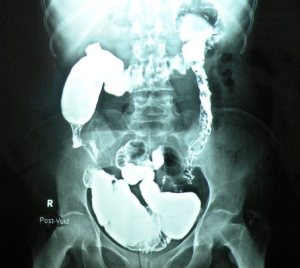

A planned right hemicolectomy became extensive resection of distal ileum and right colon. A 35 years old female admitted with a mass in right iliac fossa not resolving. CT showed a long tubular stricture in the whole of right colon, The mass regresses somewhat with conservative treatment. A barium enema showed a tight stricture reportedly in the right colon. At exploration, multiple strictures in the terminal ileum and some palpable thickening in the right colon, all of which was excised.